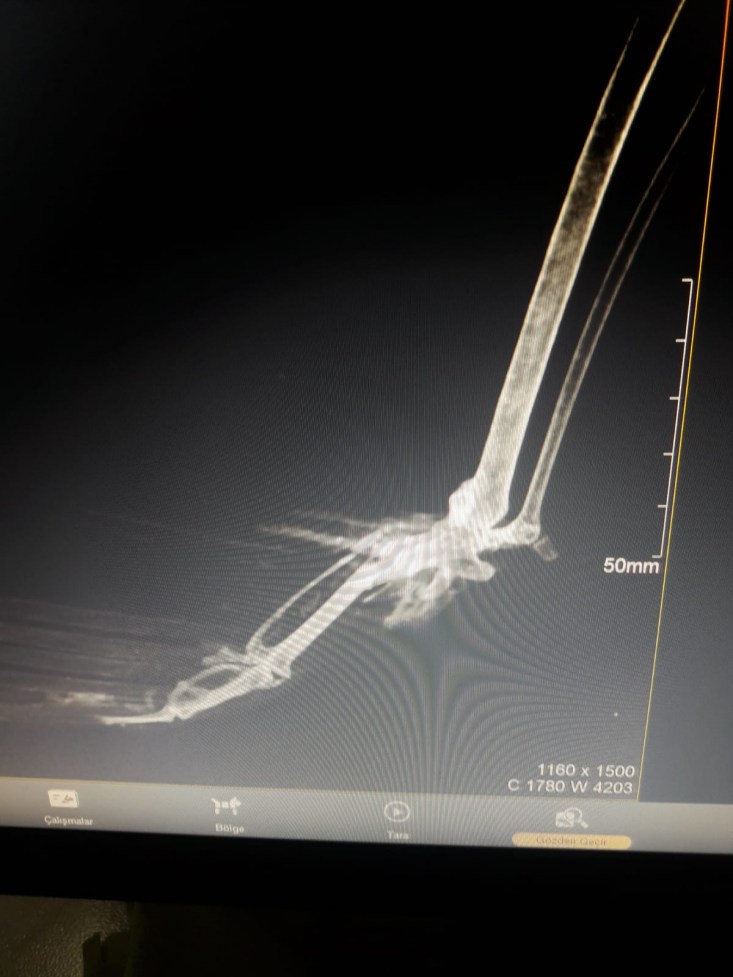

yapılmak üzere ERVET veteriner hekimliğine getirildi. Saçmalardan dolayı

kanatlarında ve kemiklerde kırılmalar meydana gelen Doğan kuşları çekilen

röntgenin ardından tedavilerine başlandı.

tarafından getirildi bu kuşumuz. Önce röntgenini çektik. Röntgeninde kemiğinin

saçma ile parçalandığını, darmadağınına yakın bir parçalanma yaşamış kemiği.

Pazar günü bunu operasyona aldık. Kırık kemiğinin parçalarını düzelttik. Kalan

kemiklerin arasındaki bağlantıyı sağladık. Önce tabi şoka giriyorlar bu durum